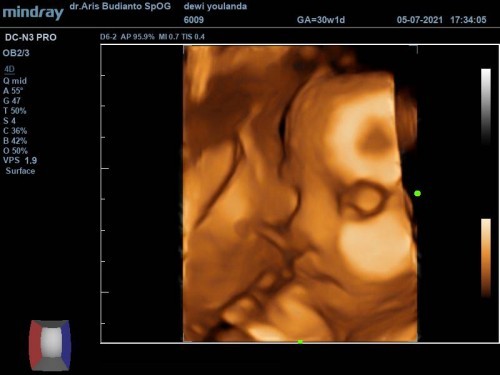

Baby girl

Cinta ayah dan bunda ❤️